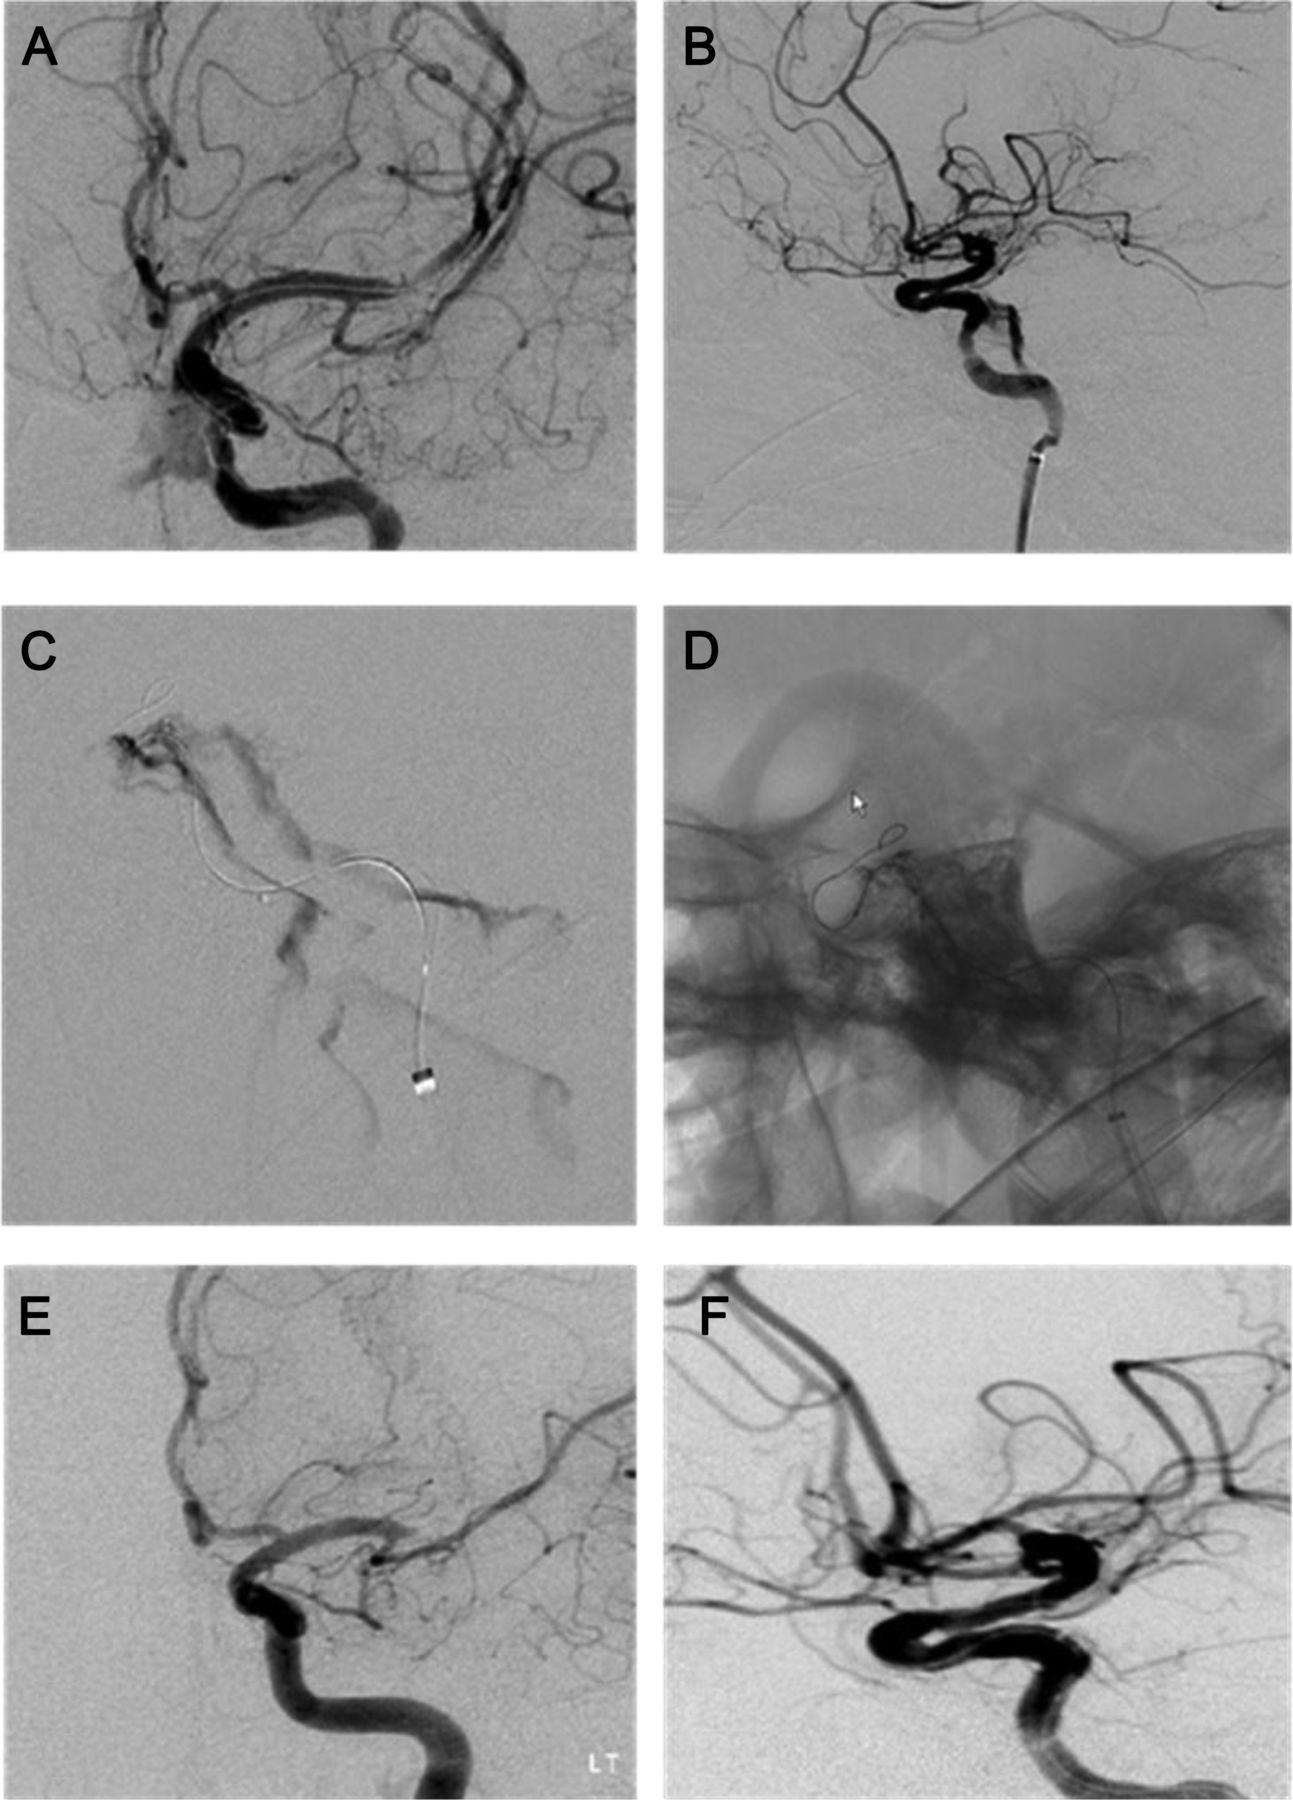

血管内治疗急性缺血性中风并发症并提出管理方法

在介入治疗急性缺血性中风周期性抗血栓形成的策略Fadi Nahab,塔里克·Kass-Hout,哈西姆·m·Shaltoni et al。

首页神经学,2012年9月24日 - 周期性管理

急性缺血性中风的周期性管理干预尼古拉斯•Tarlov Yih林粘、奥萨马o . Zaidat et al。

首页神经学,2012年9月24日 - 观点和评论